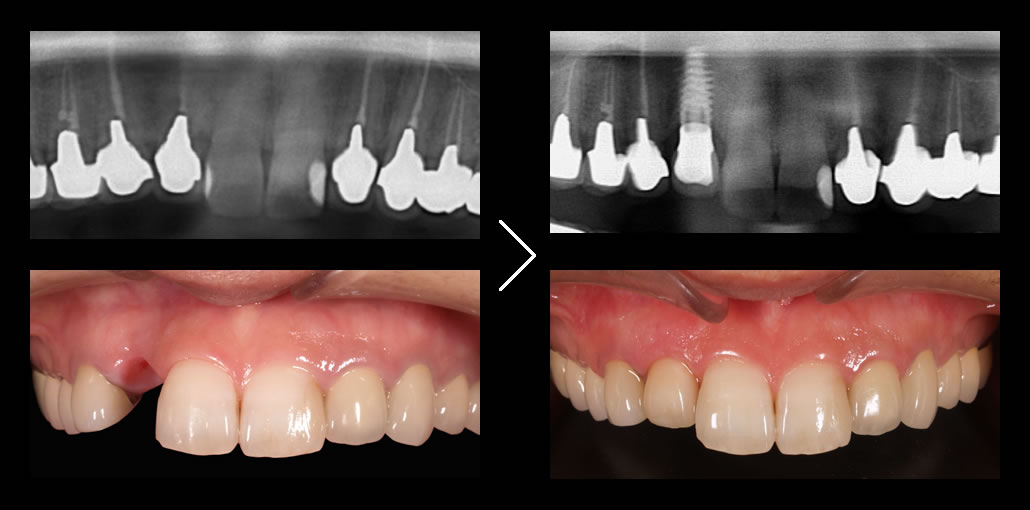

他医院では行わない精密な治療計画

オールオン4クリニックでは、必要に応じてインプラント治療前に歯肉や骨の調整を行い、綿密な診査・診断・3Dプランニング・ガイデッドサージェリーを駆使して、寸分のズレのないインプラント埋入を行います。